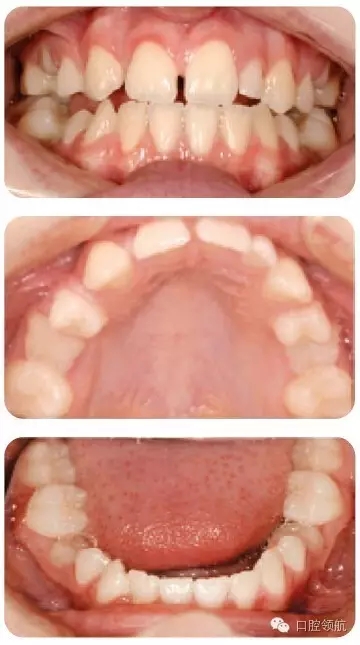

嚴(yán)重STHAG相關(guān)的主要臨床特征有哪些?(圖2.18)

● 嚴(yán)重的STHAG常與后縮側(cè)貌相關(guān),伴下前面高減小。垂直比例減小的病例常導(dǎo)致覆加深。

● 口內(nèi)特征根據(jù)只有1顆牙先天缺失的輕度病例或超過(guò)6顆牙缺失的重度病例而不同。嚴(yán)重病例通常有散在間隙和乳牙滯留。

● 常伴隨過(guò)小牙,可以是局部(釘狀側(cè)切牙)或廣泛的。

● 很多病例的滯留乳牙可以保留至成人階段。下沉的乳磨牙往往提示繼承恒牙缺失。

● 多顆牙缺失的病例,繼承恒牙缺失可導(dǎo)致頜骨發(fā)育不全,牙槽嵴狹窄。有時(shí)會(huì)出現(xiàn)側(cè)方開(kāi)牙合。